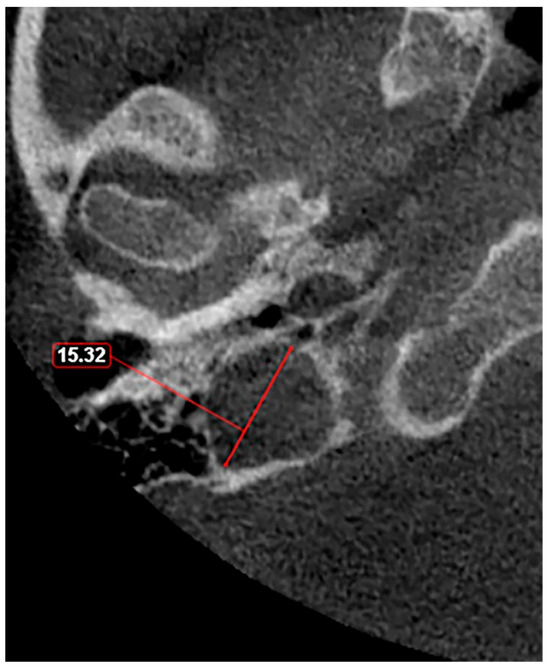

- Raghuram, K.; Cure, J.K.; Harnsberger, H.R. Condylar jugular diverticulum. J. Comput. Assist. Tomogr. 2009, 33, 309–311. [Google Scholar] [CrossRef]

- Jagtap, R.; Wazzan, T.; Hansen, M.; Kashtwari, D. Condylar jugular diverticulum: A report of 3 cases. Imaging Sci. Dent. 2019, 49, 251–256. [Google Scholar] [CrossRef]

- Parillo, M.; Vaccarino, F.; Mallio, C.A.; Quattrocchi, C.C. Right Condylar Jugular Diverticulum: Contrast-enhanced Computed Tomography Findings of a Rare Anatomical Variant of Jugular Bulb. Indian J. Otolaryngol. Head Neck Surg. 2023, 75, 2257–2259. [Google Scholar] [CrossRef] [PubMed]